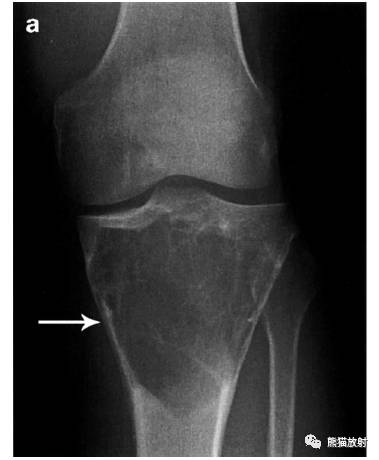

↓ 胫骨上端骨巨细胞瘤

I B:地图样、边缘清楚、无硬化缘